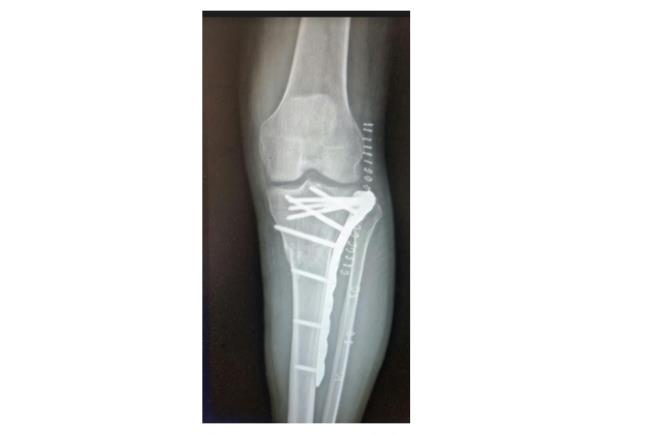

לאחר הניתוח יתבצעו טיפולי פיזיותרפיה להפעלה אקטיבית (על ידי המטופל/ת) ופאסיבית (על ידי פיזיותרפיסט/ית) של המפרק. הטיפול הפיזיותרפי נועד כדי להשיב את טווח התנועה התקין ועל כן יתבצע עד שהמפרק יחזור לתפקוד תקין או לחלופין עד הגעה לטווח הטוב ביותר אותו ניתן להשיג לאחר הניתוח. במקרים מסוימים, יהיה צורך בשימוש בסד בזמני המנוחה (כאשר לא מבוצעת פיזיותרפיה), אם כי לרוב המטרה תהיה להפעיל את האיבר כמה שיותר.אם טווח התנועה שהושג לאחר הטיפול אינו מלא, מומלץ לפנות להערכה מחודשת של אורתופד כדי להבין האם מדובר במצב הסופי והטוב ביותר אליו ניתן להגיע או שנדרשת פעולה ניתוחית נוספת.

קיבוע שבר בעצם הטיביה | באדיבות פרופ' דורון נורמן